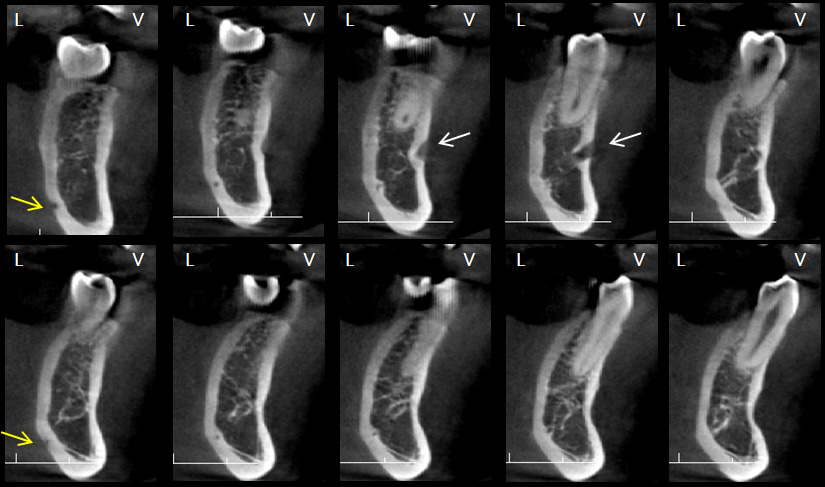

En los trabajos de Wei (16) y Krishnan (17), la variante anatómica que se observó con mayor frecuencia tanto en el lado derecho como izquierdo fue el FLL (figura 3), esto en concordancia con los resultados del presente estudio, lo que se repitió en todos los grupos etáreos. Trost (18) señaló que fueron los varones quienes presentaron mayor número de FLL en comparación a las mujeres, sin embargo, la presente investigación encontró su frecuencia en mayor porcentaje en el sexo femenino, esto podría deberse a que representaban la mayoría de la muestra. Se encontró casos con la presencia de FLL doble, no se ha hallado bibliografía que haga referencia a este tipo de variante anatómica (figura 4).

No hay mucha evidencia científica que refiera una presencia simultánea de FMA y FLL, Krishnan (17) encontró una asociación entre la presencia de ambas variantes anatómicas. En su estudio el 42,9% de los casos que presentaba FLL tenía también un FMA, este hallazgo es similar a la distribución observada en el presente trabajo (figura 6). En la muestra de este estudio se pudo encontrar combinaciones de variantes anatómicas no descritas en otras publicaciones, como la presencia de foramen doble y FLL doble en 3 casos y la relación de foramen triple y FLL encontrada en un caso (figura 7 y figura 8).